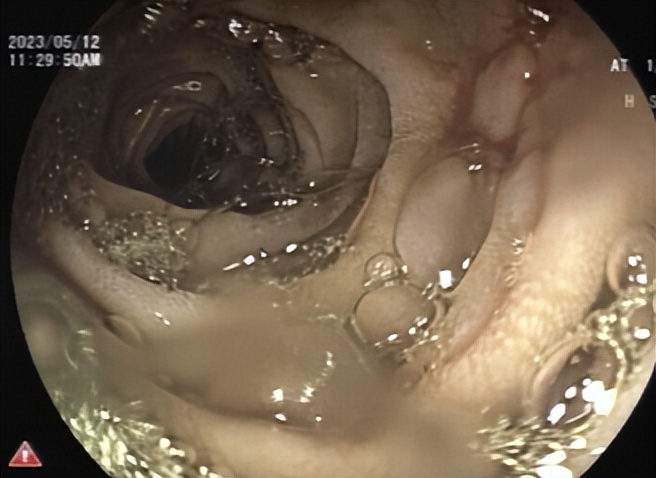

2023年5月6日和8日,哈医大一院群力院区消化内镜中心凭精湛的手法,耐心细致的操作,分次将嵌顿在十二指肠结石全部击碎,复查胃镜十二指肠肠腔通畅,无结石残留(图3、4),于爷爷终于又可以恢复正常生活了。

图4